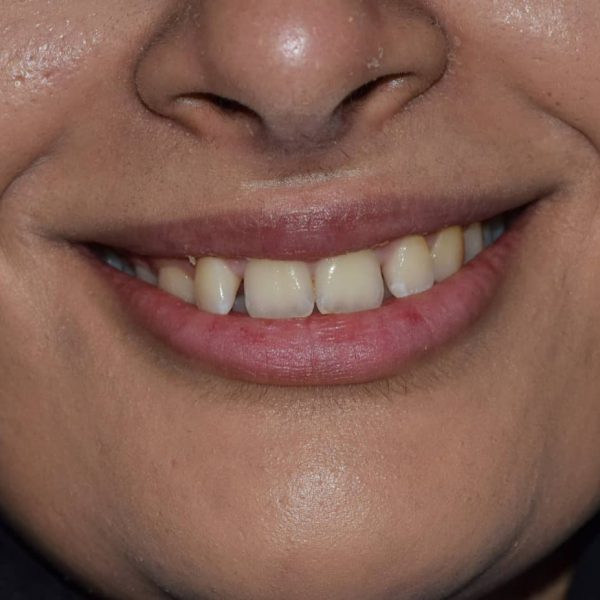

درمان: کامپوزیت ونیر دندانهای قدامی جهت بستن فواصل بین دندانی و بهبود رنگ دندانها به خواست بیمار.